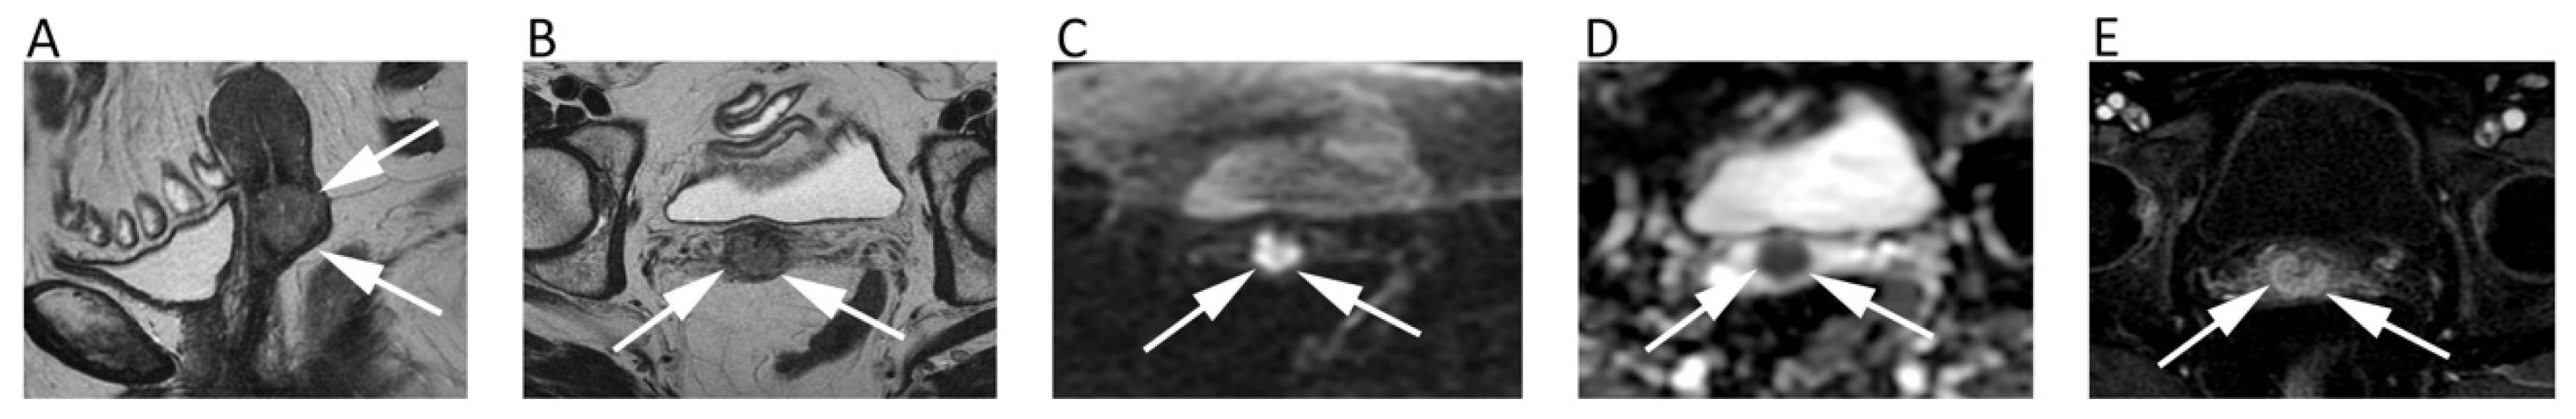

11. Prostate

| Prostate | Woo, S.; et al. Am. J. Roentgenol. 2018 [84] | Meta-analysis including 20 studies (2242 patients with histologic-proven Prostate cancer); 1.5T and 3.0T MRI. | Biparametric MRI (T2-w and DWI) and multiparametric MRI (T2-w, DWI, and DCE) had not significantly different diagnostic performance (pooled sensitivity and specificity of 0.74 and 0.90 vs. 0.76 and 0.89, respectively). |